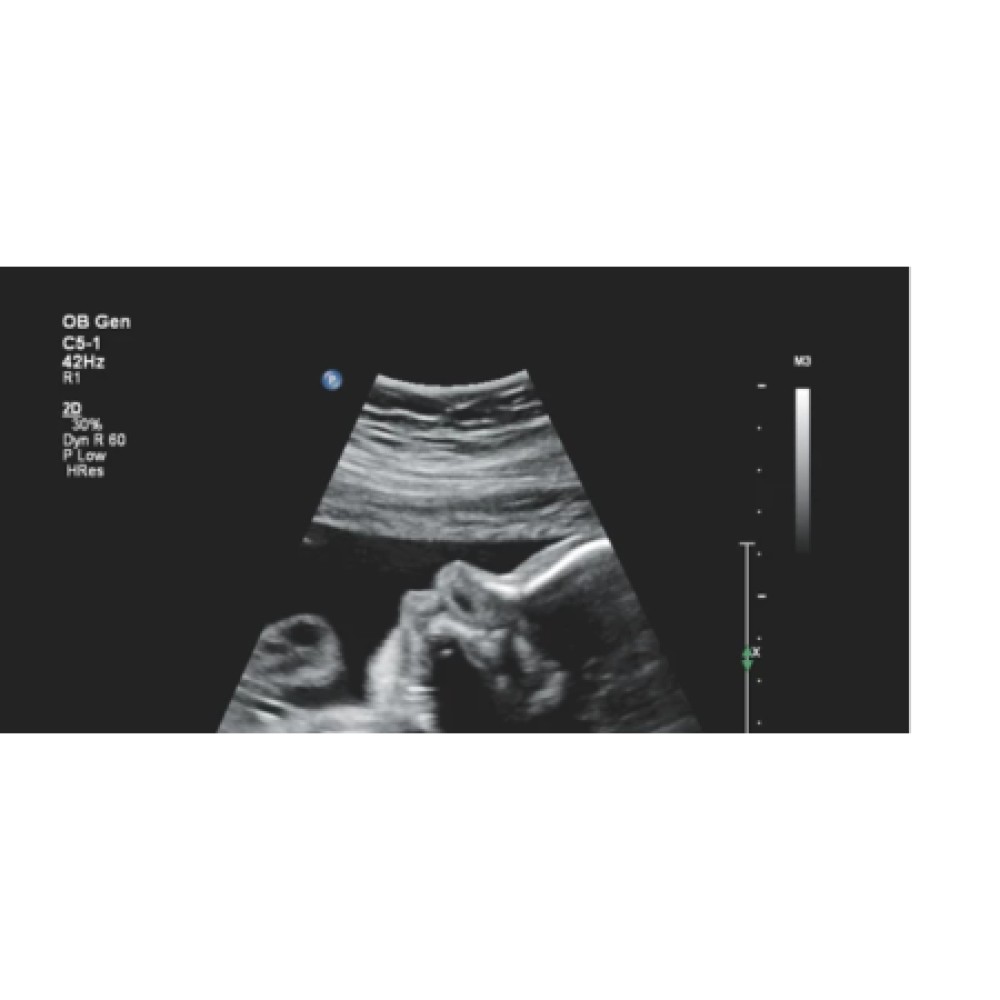

Çox yönlü istifadə: Ümumi görüntüləmə, OB/GYN, vaskulyar və kardiyak müayinələr üçün uyğundur.

C5-1: 1–5 MHz, qarın və obstetrik görüntüləmə.

Obstetrika / Ginekologiya: fetal və reproduktiv orqanların qiymətləndirilməsi.